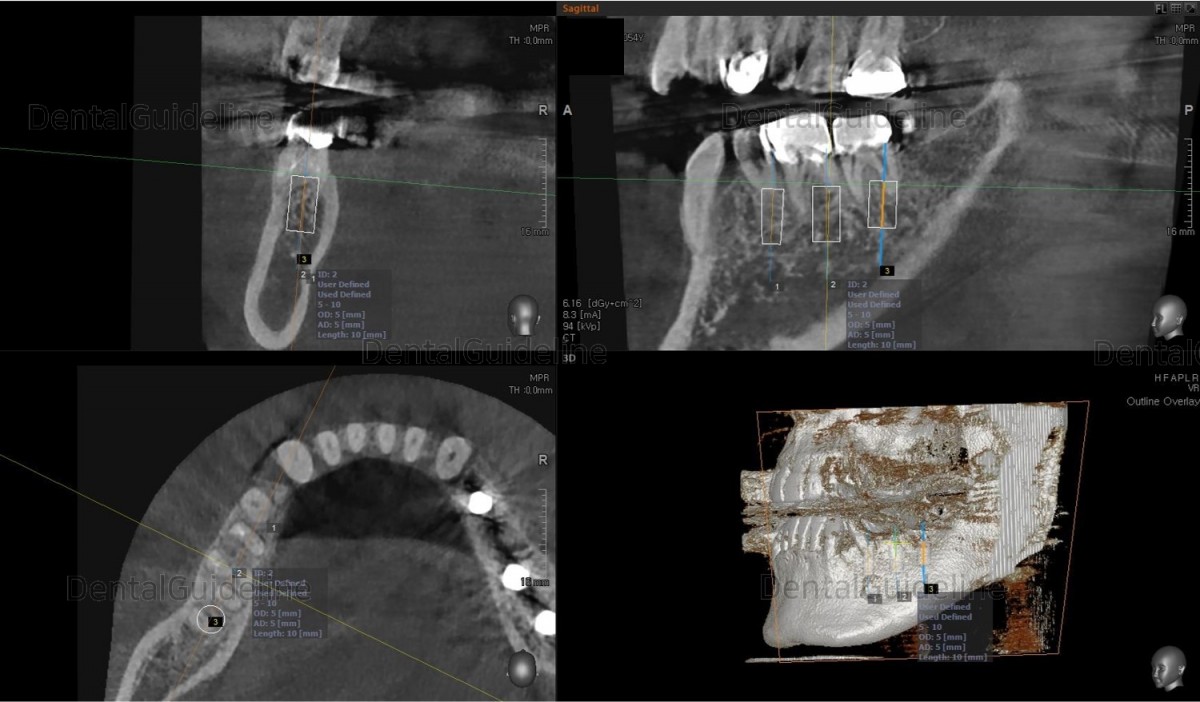

Surgery simulation to find the optimal

size, position, and direction of implants.

2nd premolar –Arum NB

Ø4.0L10 (30Ncm), 1st molar-Arum NB

Ø5.0L10 (40Ncm), 2nd molar-Arum NB

Ø5.0L10 (30Ncm),